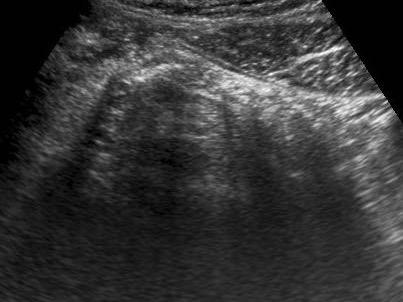

Hình ảnh Siêu âm này cho thấy ruột thừa viêm trên mặt cắt ngang (trái) và mặt cắt dọc (phải). Chương về Siêu âm trong viêm ruột thừa này được biên soạn dành cho tất cả những ai tham gia tích cực vào công tác Siêu âm bụng cấp cứu.

Siêu âm ruột thừa bình thường và ruột thừa viêm

Các đặc điểm siêu âm của ruột thừa bình thường được trình bày trong mục “Siêu âm đường tiêu hóa: giải phẫu bình thường”. Việc phân biệt ruột thừa viêm với ruột thừa bình thường thường khá dễ dàng trong hầu hết các trường hợp.

Ruột thừa bình thường – có thể quan sát thấy trong 20-30% trường hợp.

Ruột thừa viêm – có thể quan sát thấy trong 80-90% trường hợp.

Siêu âm trong viêm ruột thừa

Hình ảnh điển hình của ruột thừa viêm:

- mất nhu động

- cấu trúc phân lớp đồng tâm

- không thể ép xẹp

- đầu tận cùng bịt kín

- cấu trúc hình xúc xích

- ở vị trí cố định, thường tại vị trí đau tối đa

- đường kính tối đa trung bình là 11 mm (dao động từ 6 đến 25 mm)

- trong 35% trường hợp, sỏi phân trong lòng ruột thừa (mũi tên) được tìm thấy tại vị trí tắc nghẽn